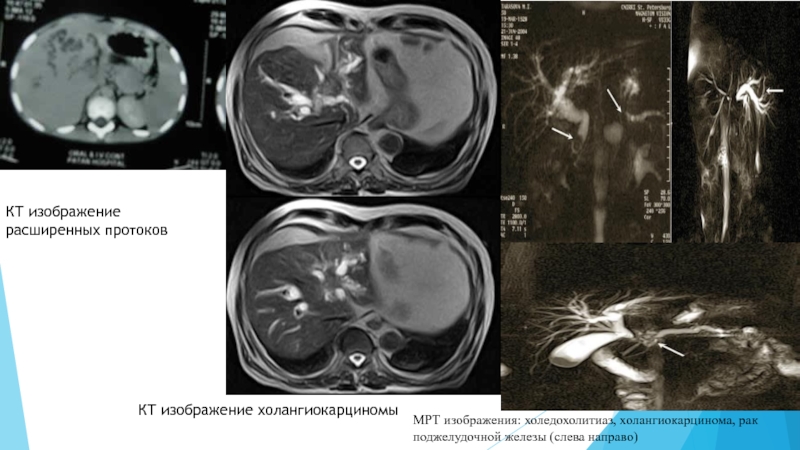

Слайд 335. Компьютерная томография и МРТ

При наличии обоснованного подозрения на рак

поджелудочной железы проводят КТ с контрастным усилением.  Высокую разрешающую способность имеет

КТ, позволяющая наряду с выявлением дилатации протоков и причины их обструкции выполнить прицельную биопсию или декомпрессивное вмешательство. В отличие от УЗИ диагностические способности метода не снижаются при метеоризме, асците, ожирении. В последние годы широкое распространение приобретает МР холангиопанкреатография, обладающая высокой точностью в диагностике причин МЖ, особенно в оценке характера и протяженности стриктур желчных путей, а также внутрипротоковых образований. Вместе с тем этот метод лишен пункционно-дренажных лечебных возможностей.

Слайд 34КТ изображение расширенных протоков

КТ изображение холангиокарциномы

МРТ изображения: холедохолитиаз, холангиокарцинома, рак

поджелудочной железы (слева направо)

КТ изображение расширенных протоковКТ изображение холангиокарциномыМРТ изображения: холедохолитиаз, холангиокарцинома, рак поджелудочной железы (слева направо)